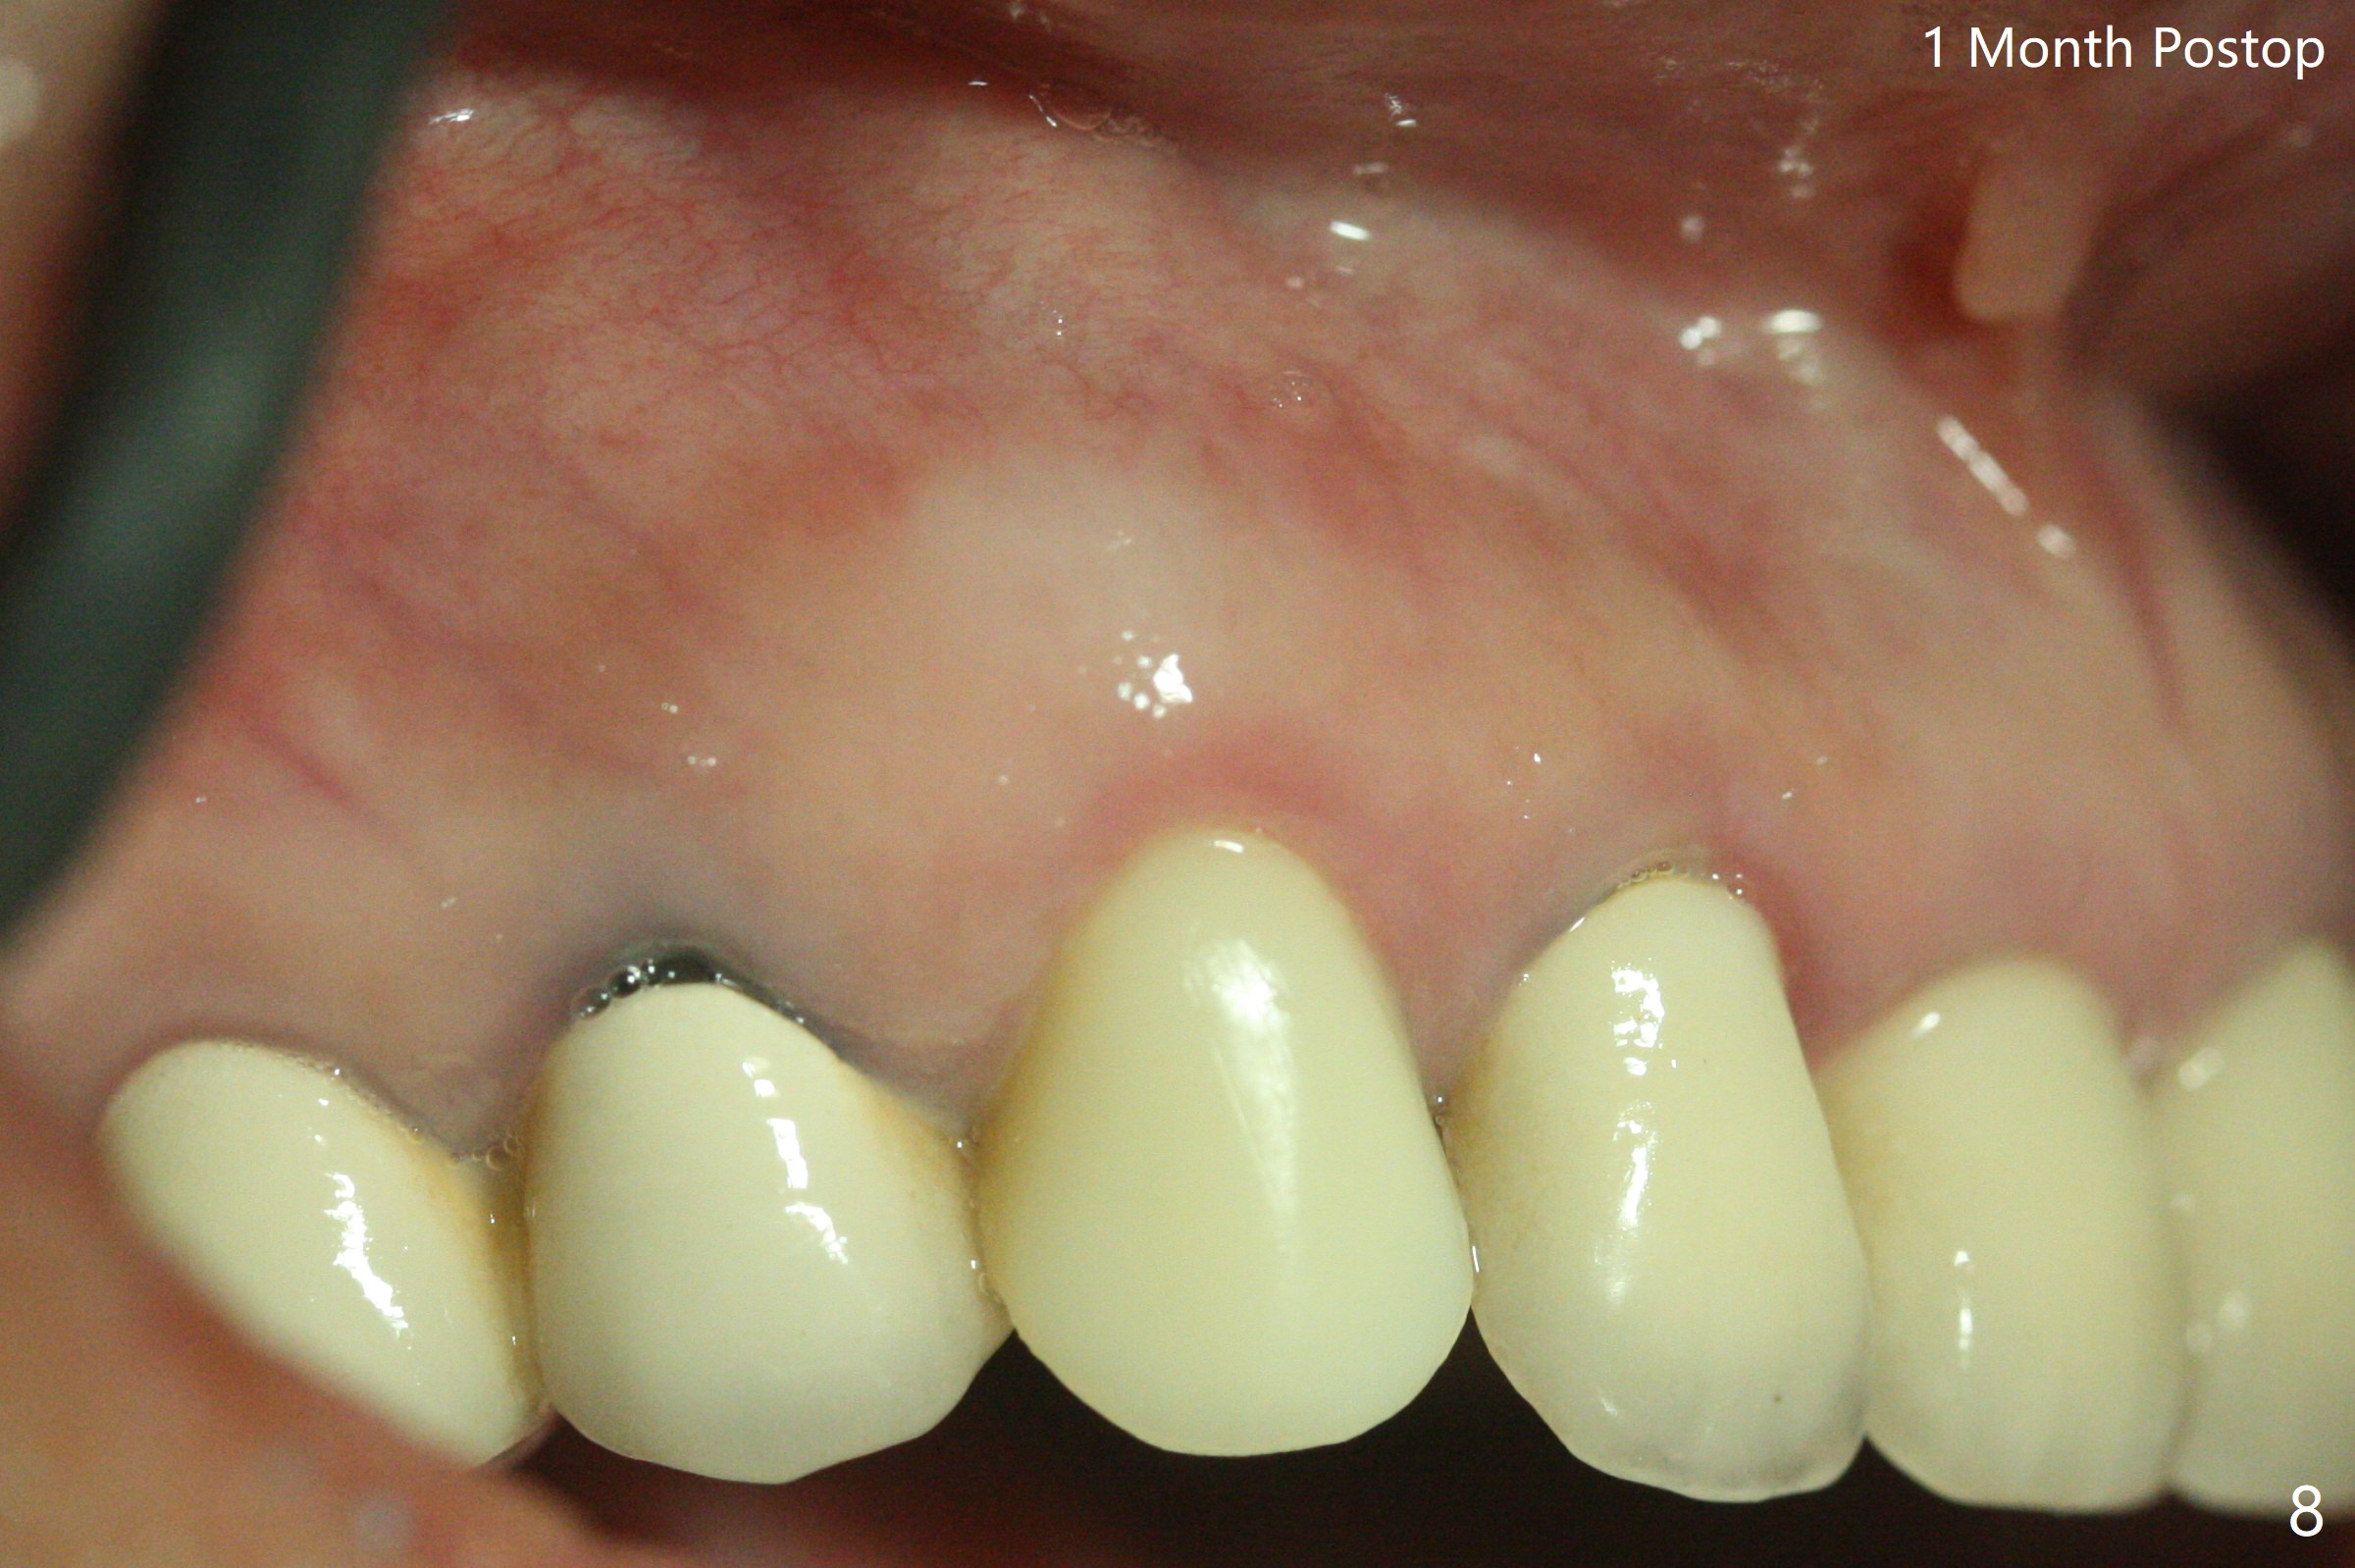

防止拔牙后颊侧骨板萎缩最有效方法是保留部分牙根,例如颊侧(外形象盾牌,简称盾,socket shield (S)),但是制备特别麻烦,尤其是上尖牙。60岁女右上3颊侧骨板隆起(图一至三:*),但是相当狭窄(上下方向),预计强行拔除,势必损失颊侧骨板,造成颊侧塌陷,准备保留盾,如图三红虚线,图六(术后3D长轴断面(十字架:植体))S代表。其实术中试图将整个牙根一起拔除,但是仿佛不行,只好静下心来分根,制备盾,不过困难重重,尤其是除去根尖(防止残余感染),最长外科裂钻似乎达不到根尖,取出后者,颊侧根尖骨板穿孔(图七:箭头)。然后腭侧钻洞(图四),当最后一个钻头保持原位时,在颊侧根尖穿孔处植入粘性骨粉(从牙槽窝口进入,原本粘性骨粉为了修复大面积颊侧缺损用(万一需要强行拔除)),然后才把一段式植体植入(图五),在其余空间填入骨粉,稍微制备基台,制作临时牙冠,最后在牙槽窝开口塞入PRF膜,衬里牙冠,不暂时取出牙冠,衬里相当于临时粘固剂。术后一个月牙根片段和临时牙冠维持良好的牙龈外形(图八,九);术后两个月病人嫌尖牙龈端太尖太长,临时牙冠龈端调整(图十,十一),但愿一个月后龈缘合乎病人期望。